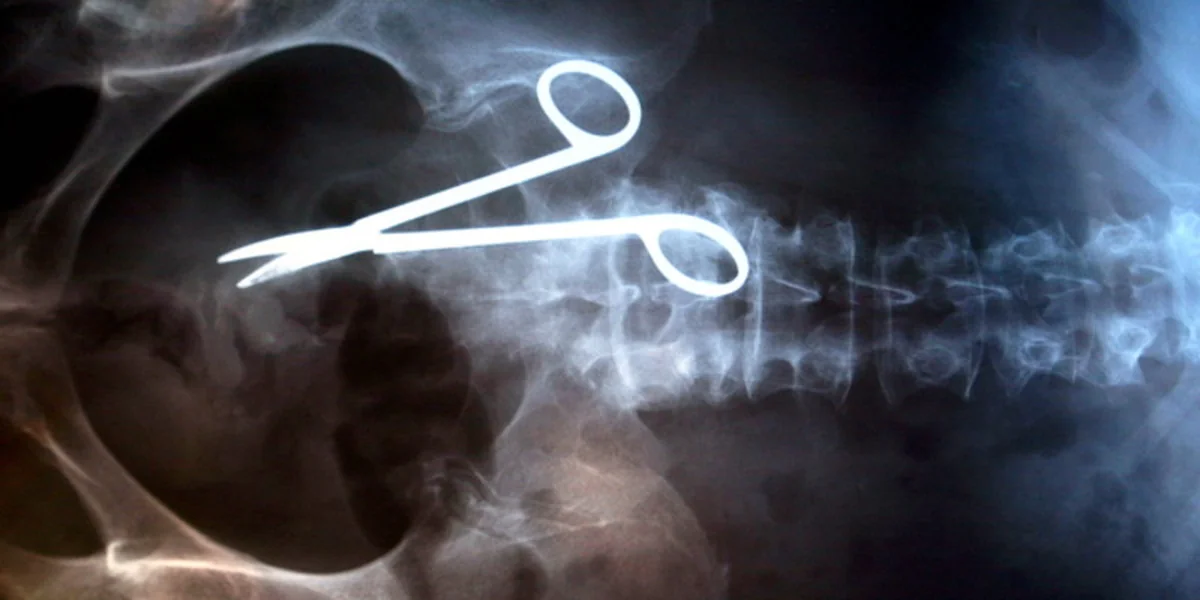

Das Gesetz bietet mehr Schutz vor groben Ärztefehlern. Bild: ap

Die inhaltlichen Neuerungen bleiben weit hinter den Erwartungen der Opposition und vor allem der Patienten- und Verbraucherschutzverbände zurück. So sieht der Gesetzentwurf zwar vor, dass künftig bei groben Behandlungsfehlern - also etwa der Amputation des rechten statt des linken Fußes - die Beweislast beim Arzt liegt. Das aber entspricht schon heute zumindest der gängigen Rechtsprechung.